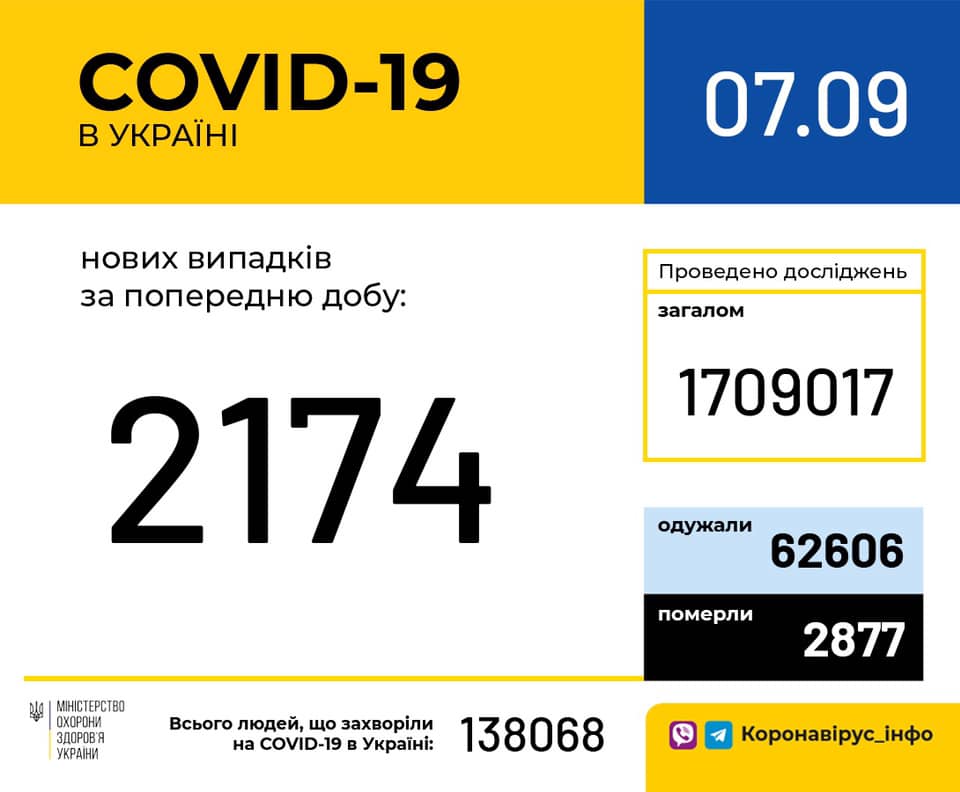

Більше 3 тисяч випадків захворювання на коронавірус зафіксували в Україні за добу

11.09.2020 09:37